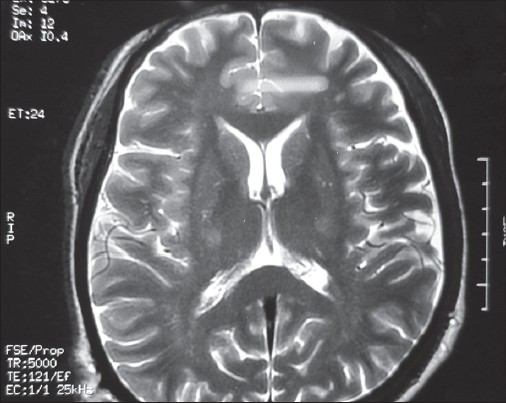

Cerebrospinal fluid (CSF) study was normal except for a marginal protein rise (51 mg/dl; normal 20-40 mg/dl). Syphilis serology by treponema pallidum hemagglutination assay, rheumatoid factor, antinuclear factor (ANF), antinuclear antibody, and ANF profile (including antineuronal nuclear antibody type 1), antiganglioside antibodies, acetylcholine receptor antibodies and human T-cell lymphocytotropic virus type 1 (HTLV-1) antibodies were all negative. Lyme serology was not done as Lyme disease is not common in India and so facilities for testing were not available. Serum lead level was normal. MRI of the corticomedullary junction and cervical spine, with and without contrast, ruled out any compressive myeloradiculopathy. MRI brain showed hyperintensity in bilateral corticospinal tract in the region of internal capsule, which was classical of ALS [Figure 3]. A final diagnosis of ALS secondary to HIV was made. He was administered new HAART regimen comprising of zidovudine, lamivudine, and ritonavir (saquinavir was discontinued due to its high dose requirement, which had led to poor adherence previously). Strict adherence to treatment was ensured after counseling sessions of the patient and education of his family members regarding the importance of regular intake of drugs in this patient. Alongside, he was started on riluzole 50 mg twice a day. Follow-up after 3 months revealed marginal improvement in limb muscle weakness, but no improvement in bulbar function. | Figure 3: Hyperintensities in both corticospinal tracts in the region of internal capsule